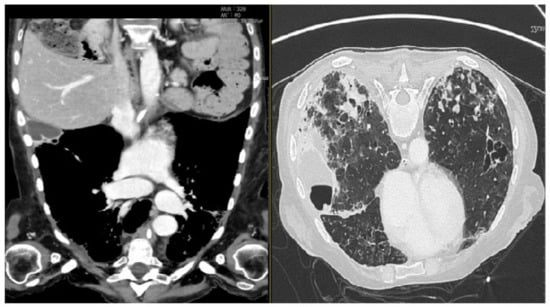

CT scan windows showing metastasis and inflammatory phenomena on both sides of the lung. (On the left, axial parenchymal lung section. On the right, axial lung window). During hospitalization, bacterial pneumonia began, worsened by secondary viral (Cytomegalovirus) and fungal pneumonia. The patient received a triple antibiotics course with an antiviral, an antifungal, and systemic and local inhalational corticosteroids. However, despite the medical therapy, the chest condition deteriorated progressively (Figure 4).